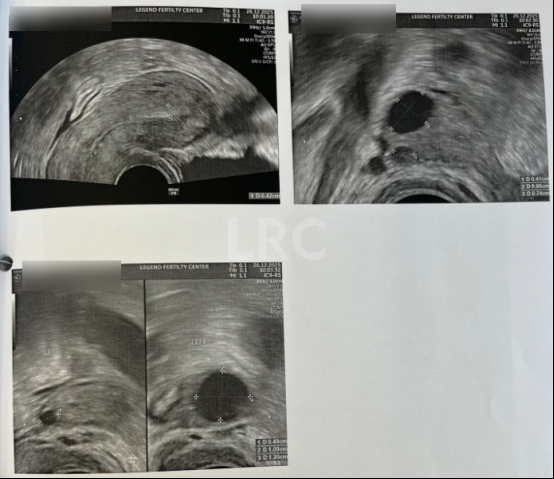

月经第二天 促排第一天

阴超检查:基础卵泡 2 颗

- 右侧卵泡 1 颗 (6mm)

- 左侧卵泡 1 颗 (7.5mm)

促排第三天

阴超检查:

- 右侧卵泡 2 颗 (9,4mm)

- 左侧卵泡 2 颗 (11,5mm)

子宫内膜厚度:4.2mm

促排第六天

- 右侧卵泡 2 颗 (13,9mm)

- 左侧卵泡 2 颗 (17,7mm)

子宫内膜厚度:4mm

促排第十天

- 右侧卵泡 2 颗 (20,15mm)

- 左侧卵泡 2 颗 (23,7mm)